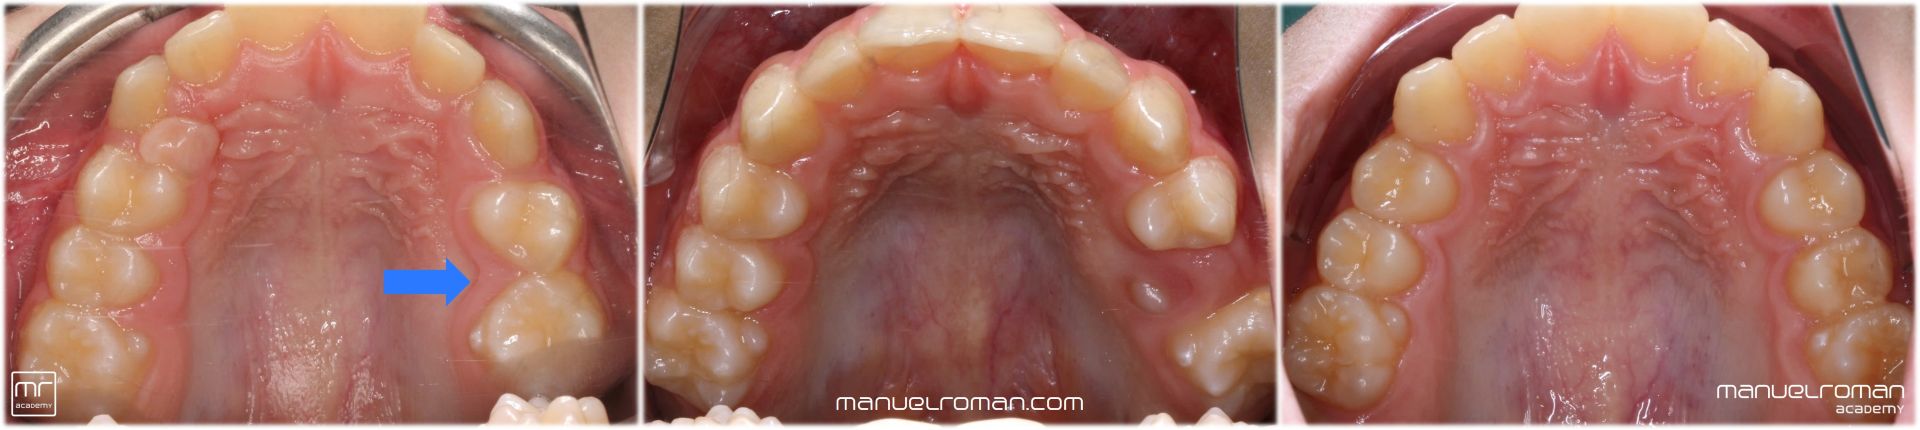

La Masterclass de ortodoncia invisible y ortopedia en niños impartida por el Dr. Manuel Román está dirigida a aquellos dentistas, odontopediatras y ortodoncistas que quieran especializarse en el tratamiento precoz, en niños y pacientes en crecimiento con alineadores.

Aprenderás a tratar pacientes desde los 4 años con ortodoncia preventiva e interceptiva hasta la adolescencia.

Serás un experto en ortopedia dentofacial, conocerás todos los secretos sobre el tratamiento de la mordida cruzada posterior y el avance mandibular en clases II (Spark, Invisalign, Angel, Twin Block, Herbst) junto con el resto de maloclusiones como tratamiento de la clase III o la mordida abierta anterior (y hábitos).

También aprenderás a resolver los problemas de erupción con los que nos encontramos en erupción mixta: dientes ectópicos, falta de espacio, desarrollo de las arcadas, transposiciones dentarias, etc. No solo veremos caninos incluidos, también incisivos, premolares y molares incluidos.